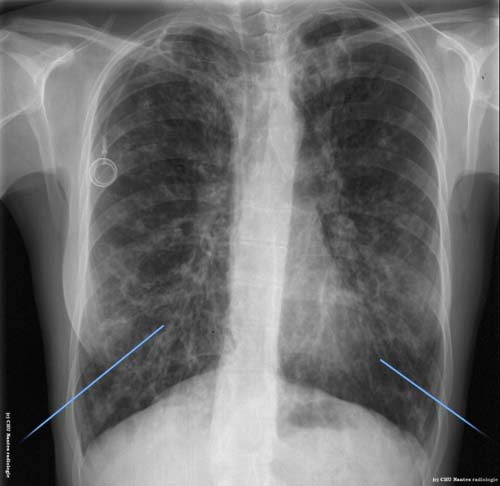

Dilatations des bronches

Aspect de poumon sale avec images en rails et en anneaux bilatérales correspondant aux parois           bronchiques épaissies et dilatées : DDB sur mucoviscidose